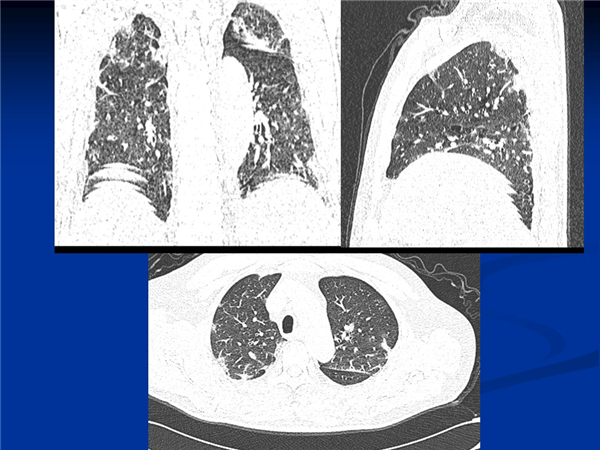

【病例分享】新型冠狀病毒感染肺部CT影像4例(常德市第一人民醫(yī)院)